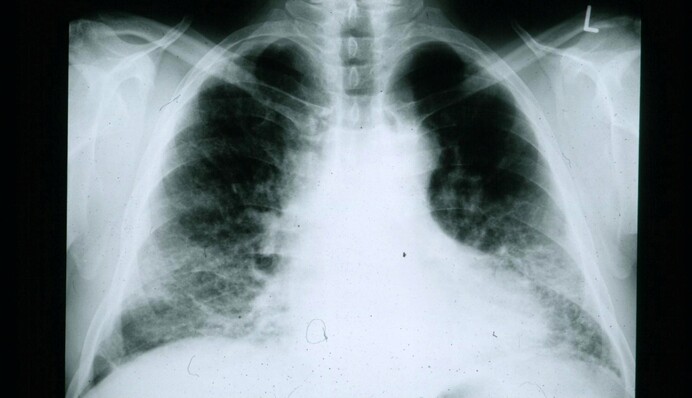

Фіброз - це стан, при якому у легенях розростається сполучну тканина. Нарости заважають органу виконувати свою основну функцію з перекачк повітря і розвивається легенева недостатність. Цей стан невиліковний. Раніше медики вважали, що фіброз провокують запалення, травми та інфекції. Але зараз вчені почали говорити вже про біологічні причини захворювання.